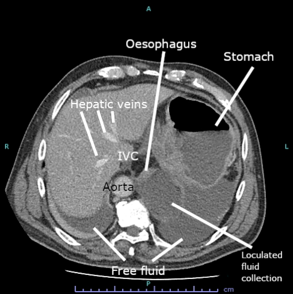

CT Bleeding Study

Author: Sadia Noreen

Date Published: Jan 20, 2025

Disease Specialty: Gastroenterology

Image Type:

CT Scan